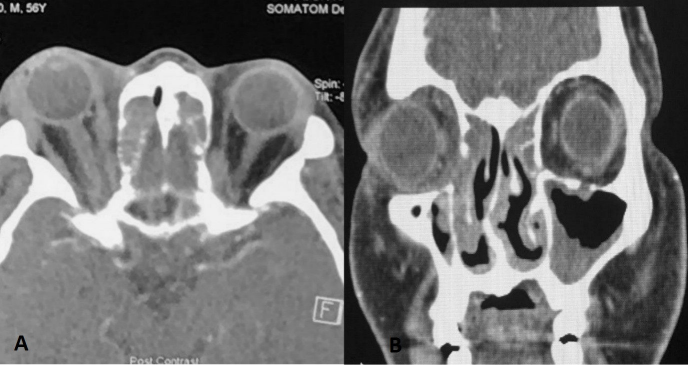

Computed tomography (CT) scan of the orbit and paranasal sinuses (Figure 2 [Fig. 2]) revealed right periorbital soft tissue swelling and enhancement with enlargement of the right lacrimal gland. The right extraocular muscles were bulkier compared to the left with fat streakiness in the extra and intraconal spaces. There was soft tissue density within the frontal sinuses, ethmoidal air cells, and mucosal thickening in both maxillary sinuses with evidence of erosion of the right lamina papyracea. Both osteomeatal complexes were obliterated. The nasal endoscopy findings showed deviated nasal septum to the right, mucinous discharge from posterior ethmoid sinus in the right nostril with obliteration of osteomeatal complex in both nostrils suggestive of pansinusitis. No evidence of tumour or polyp was seen.

Figure 2: CT scan imaging of the orbit and paranasal sinuses: A) Axial view (left) demonstrated right periorbital soft tissue swelling with right extraocular muscle bulkier compared to left side. There was enlargement of the right lacrimal gland. Soft tissue density was seen within ethmoidal air cells. B) Coronal view (right) demonstrated soft tissue density in the frontal sinus, ethmoidal air cells and mucosal thickening in both the maxillary sinuses with obliteration of both osteomeatal complex. There was erosion of the right lamina papyracea.